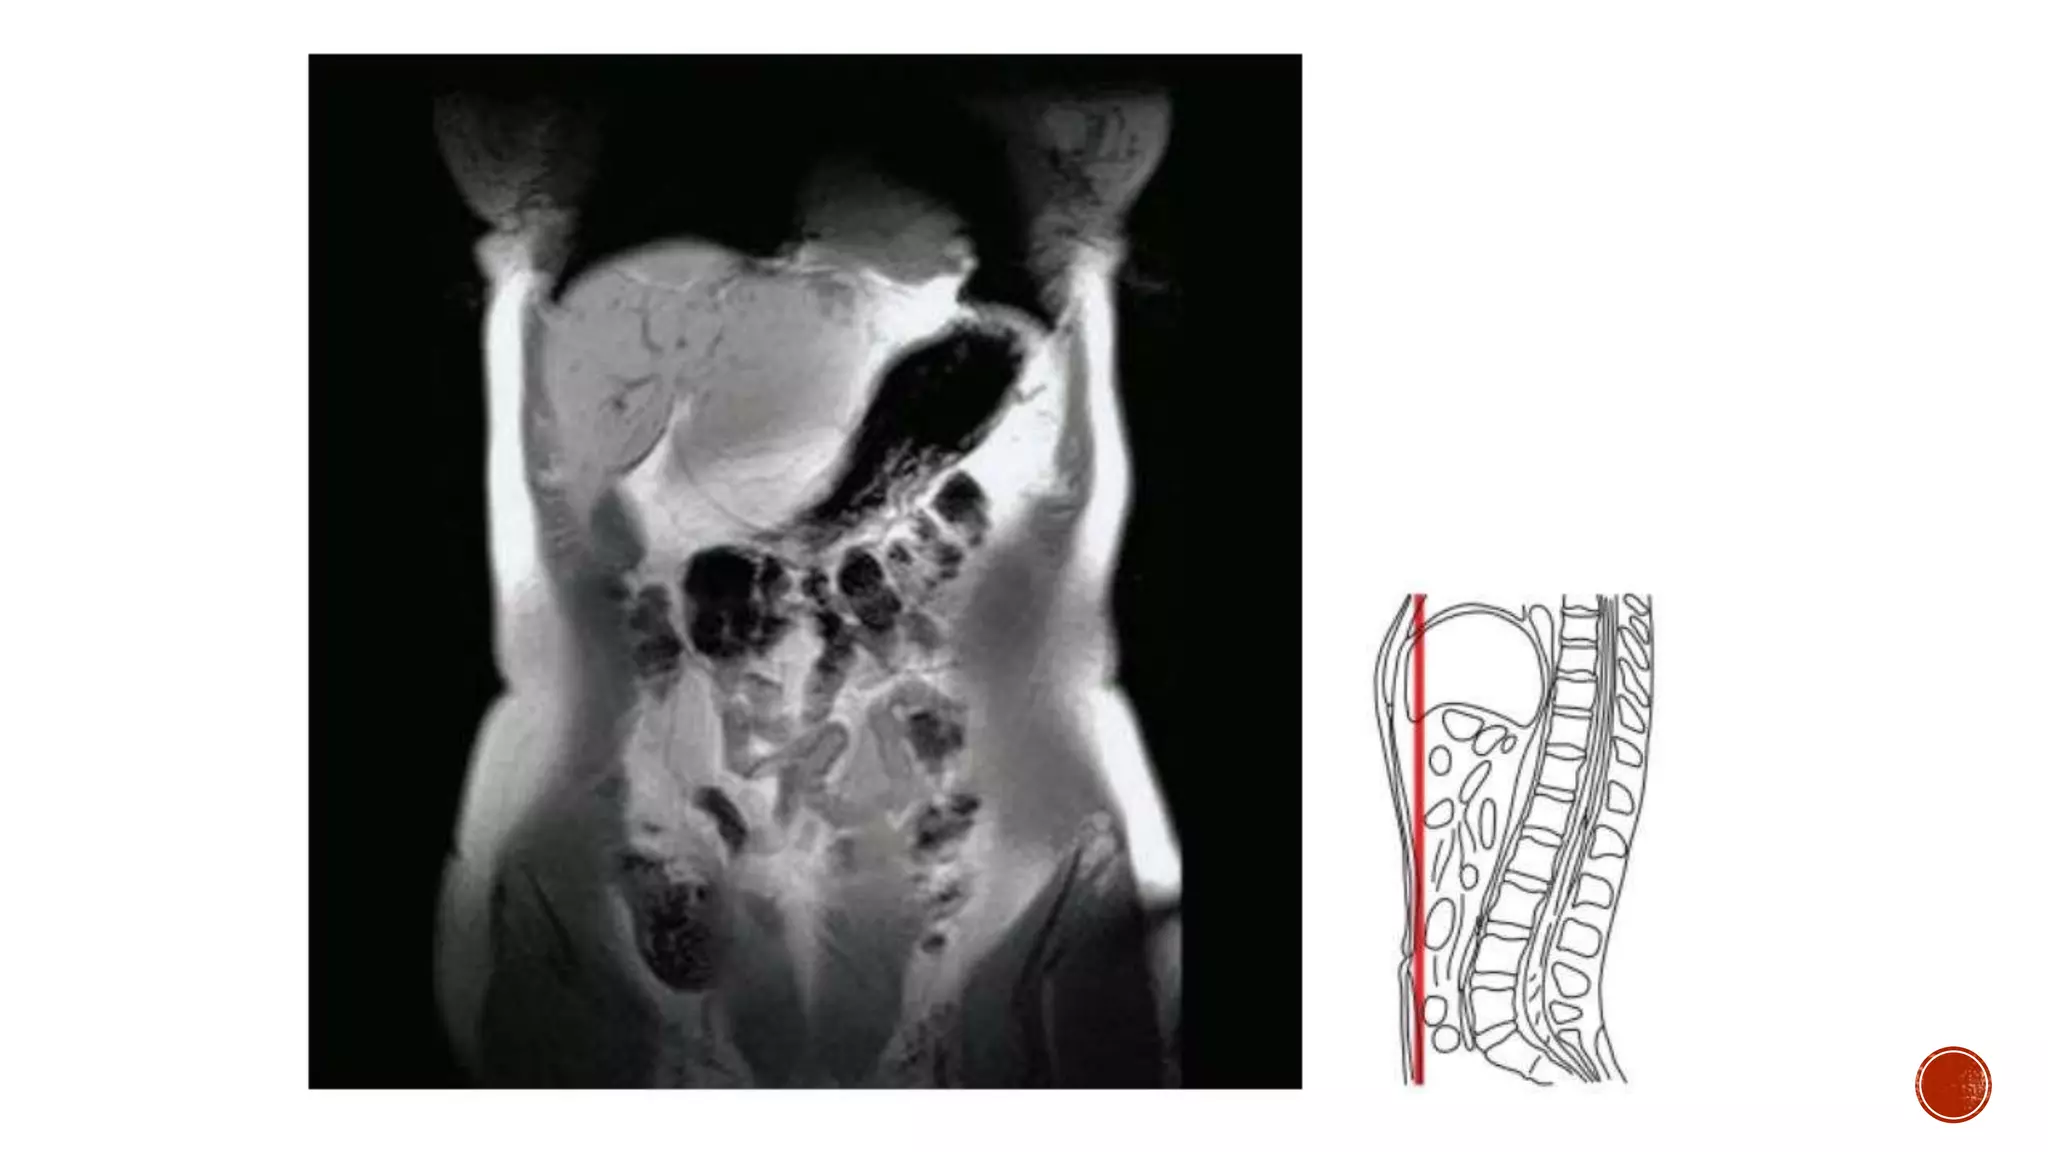

The document describes the anatomy of the abdomen and pelvis region of the human body. It lists over 40 structures and their locations, including major organs like the liver, kidneys, intestines, blood vessels and muscles of the abdominal wall and pelvis. The structures are grouped into sections focusing on different anatomical areas like the abdomen, retroperitoneum, pelvis and gluteal region.